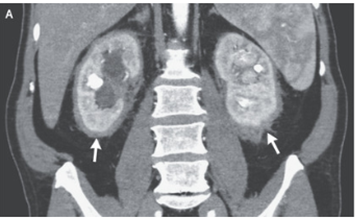

73歳男性。1か月にわたる倦怠感と全身の骨痛を訴え救急外来を受診した。 身体所見では肝脾腫が無いことを含め特記すべき所見を認めなかった。 採血所見ではWBC 1…